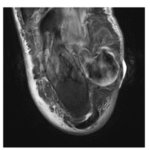

1. Abstract

Cerebrotendinous xanthomatosis (CTX) typically presents with infantile diarrhea, juvenile cataracts, and tendon xanthomas. We report a diagnostically challenging case of late-onset CTX in a 48-year-old male presenting with isolated progressive